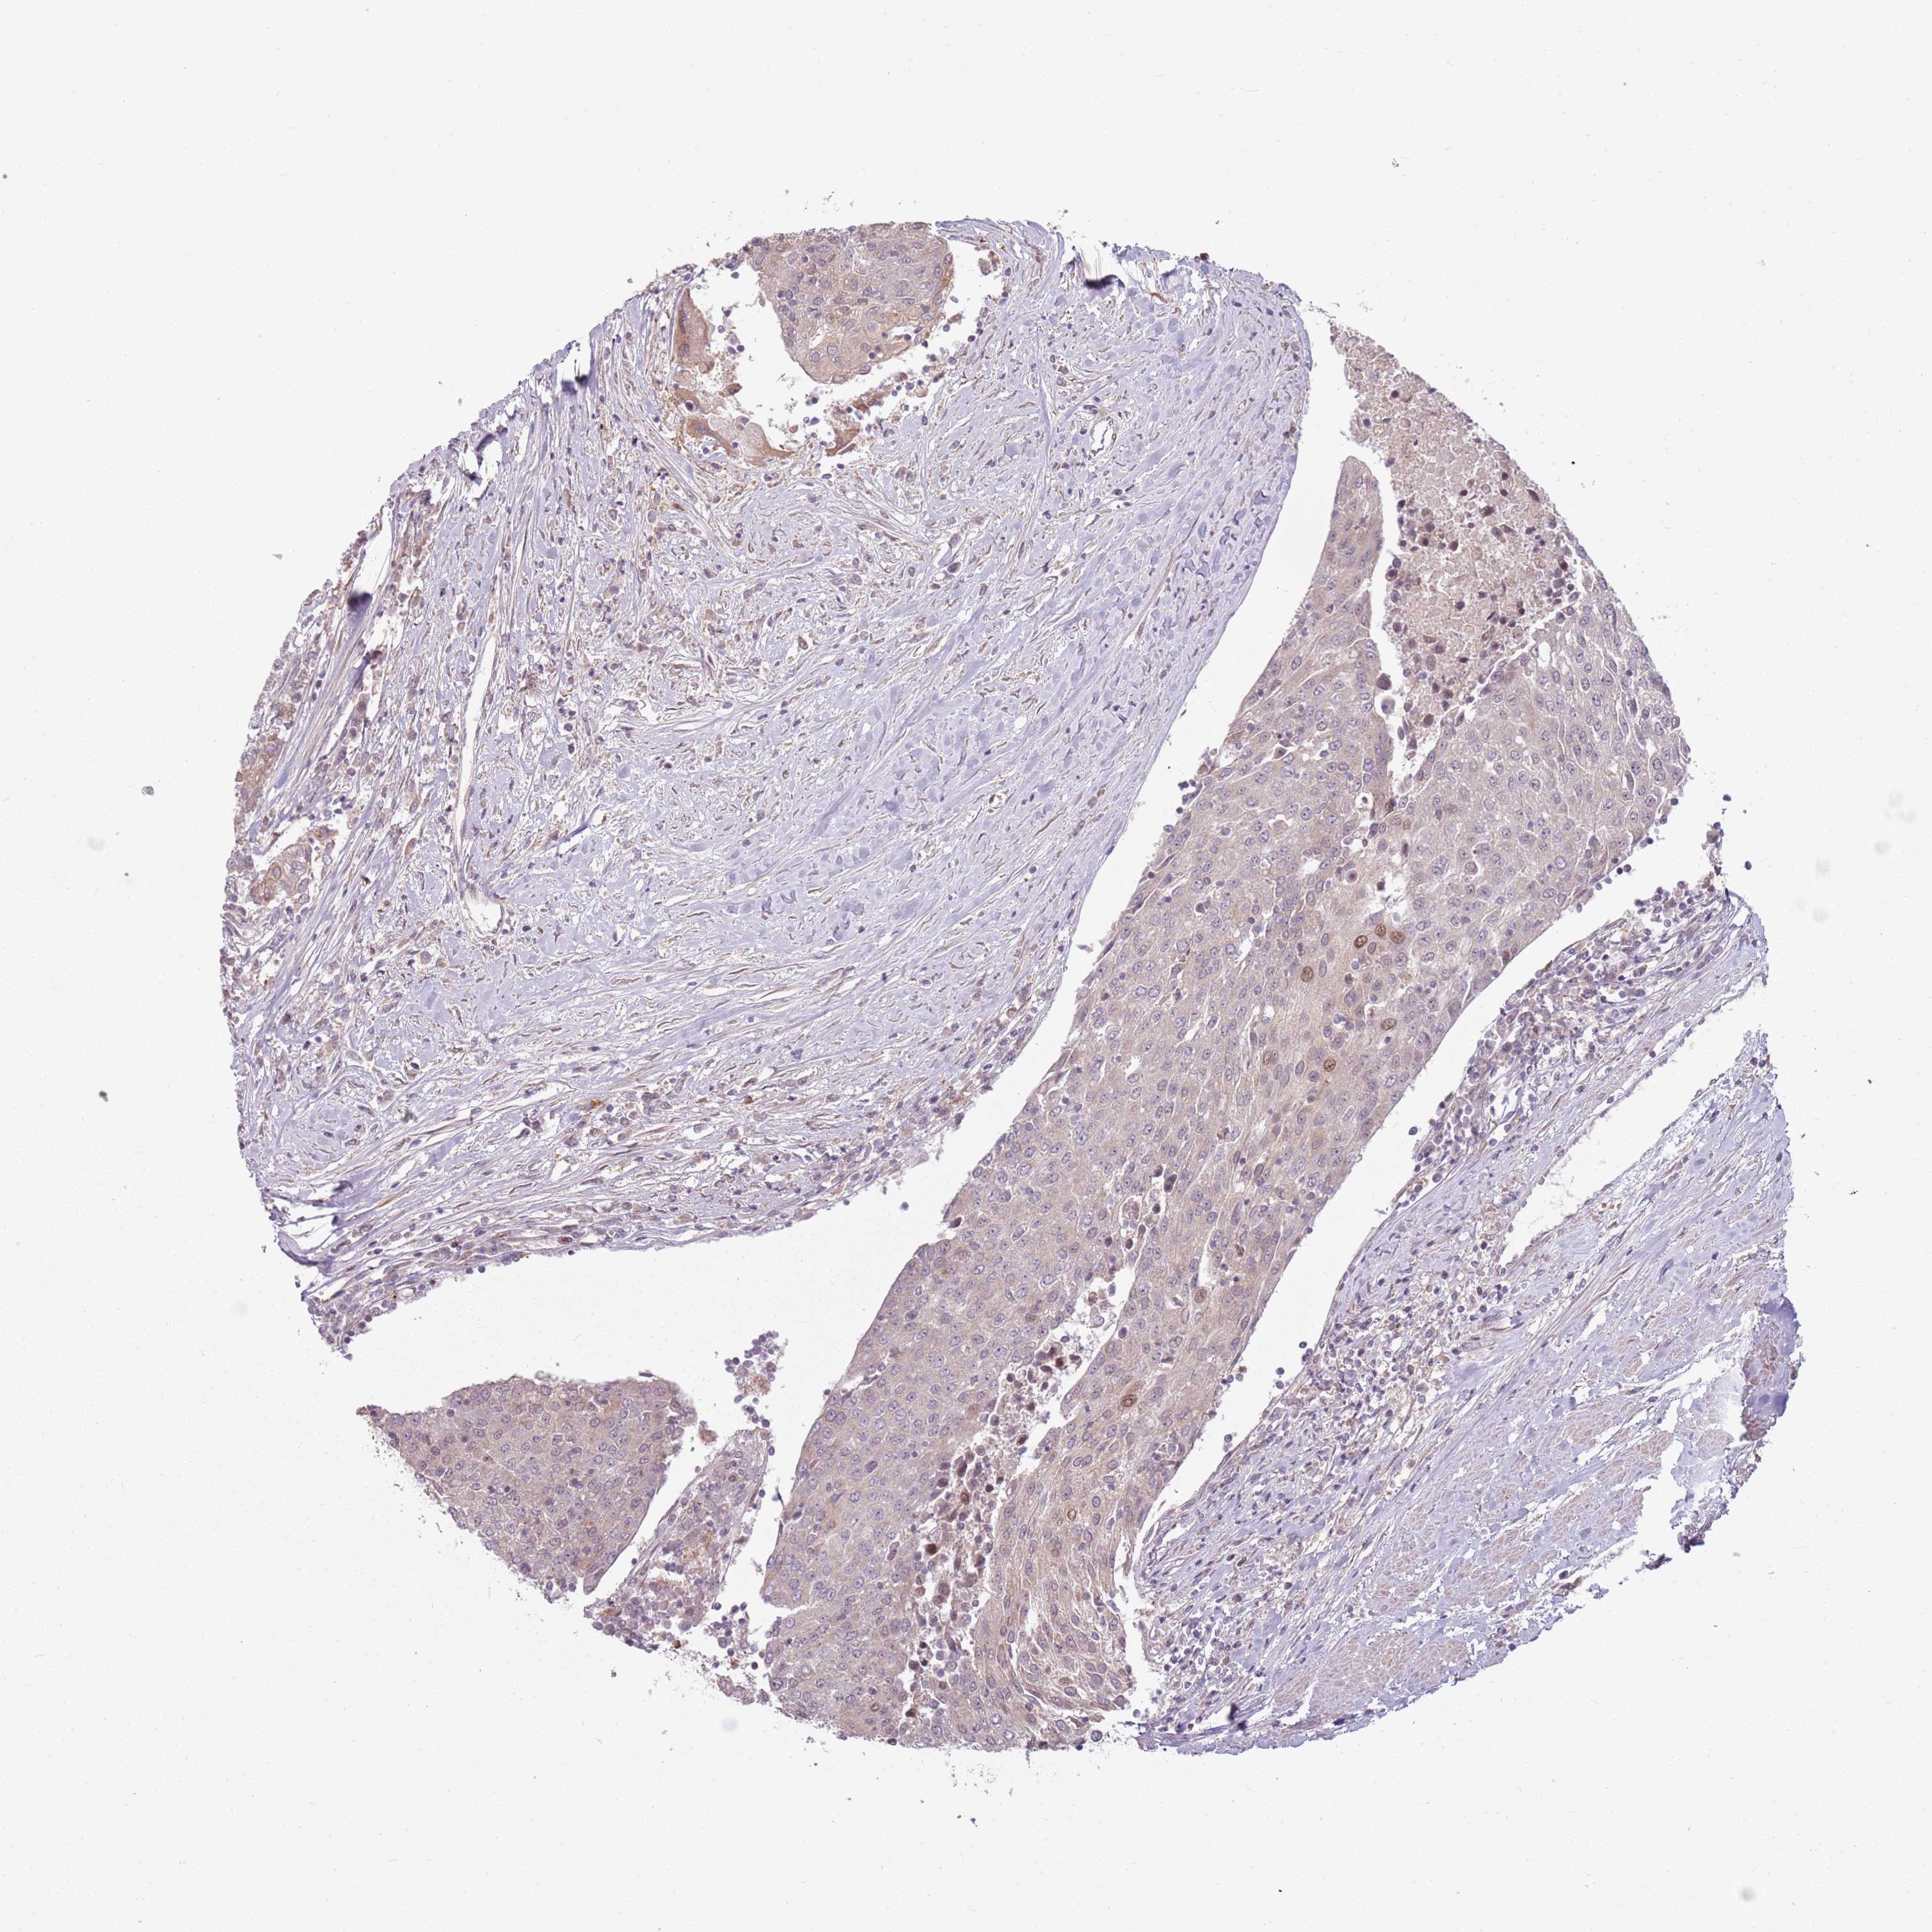

UROTHELIAL CANCER - Protein expressioni

A mouse-over function shows sample information and annotation data. Click on an image to view it in a full screen mode. Samples can be filtered based on level of antibody staining by selecting one or several of the following categories: high, medium, low and not detected. The assay and annotation is described here.

Antibody stainingi

Antibody staining in the annotated cell types in the current human tissue is reported as not detected, low, medium, or high, based on conventional immunohistochemistry profiling in selected tissues. This score is based on the combination of the staining intensity and fraction of stained cells.

Each image is clickable and will lead to virtual microscopy that enables deeper exploration of all samples and also displays staining intensity scores, fraction scores and subcellular localization as well as patient and tissue information for each sample.

Antibody HPA046065

Staining

High

Medium

Low

Not detected

Intensity

Strong

Moderate

Weak

Negative

Quantity

>75%

75%-25%

<25%

None

Location

Nuclear

Cytoplasmic/membranous

Cytoplasmic/membranous,nuclear

Urothelial carcinoma, High grade

Urothelial carcinoma, Low grade